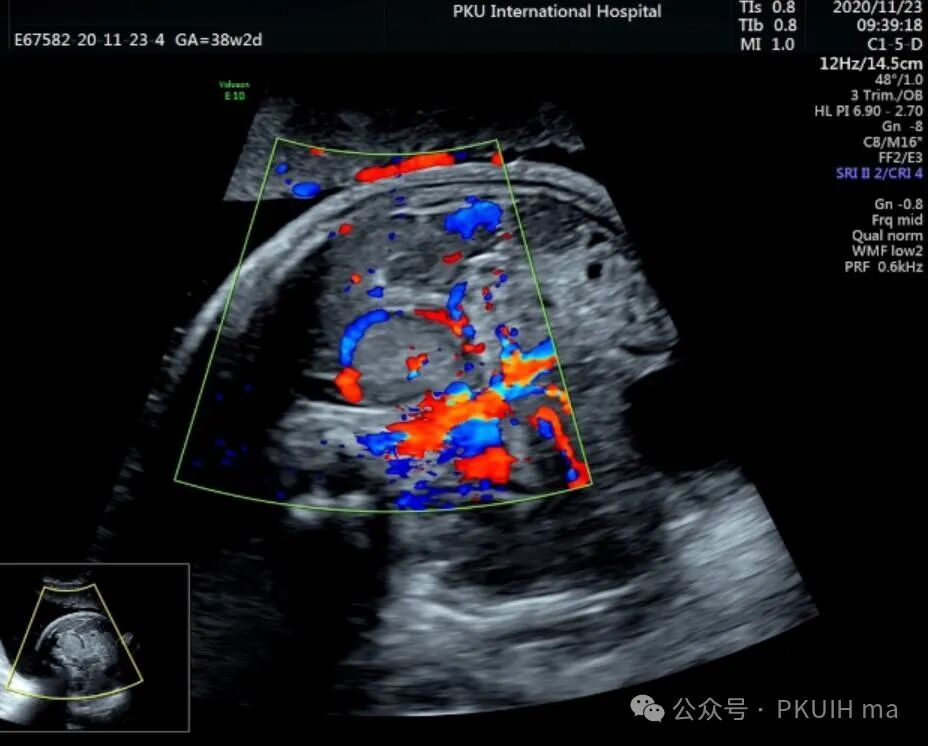

神经母细胞瘤是儿童时期最常见的肿瘤之一,其发病率为1/10,000 -30,000儿童。神经母细胞瘤可在妊娠晚期被诊断出来。产前诊断的肿瘤往往较小,90%涉及肾上腺。囊性和实性区域是典型的,可伴有出血和坏死。囊性病变预后较好。神经母细胞瘤可有微钙化,伴有声影、完整包膜和造成肾脏下移。这些肿瘤可能出现在颈部、胸部或腹部椎旁交感神经节的其他部位。引起气道压迫的宫内病变已有报道。肾上腺肿块伴肝肿大提示神经母细胞瘤的诊断。

上图是一例在孕晚期发现的肾上腺占位,生后病理证实为神经母细胞瘤的患儿,生后及时做了治疗预后非常好,目前宝宝各项指标都很好。

这几年我们在孕晚期发现有3例神经母细胞瘤胎儿,预后都很好。在孕晚期超声中建议常规扫查下胎儿双肾区